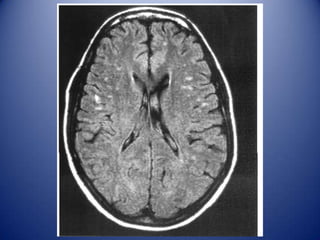

MRI white-matter lesions in NPSLE

↑ signal in Τ2 / FLAIR

• Localized in subcortical and periventricular

white matter and frontal-parietal lobe (70–80%)

• Prevalence 50–60% of all patients with NPSLE

…but 18–40% of non-NPSLE

…no correlation with a particular NP syndrome

• Cerebral atrophy, number and size of WML and cerebral infarcts

correlate with severity of cognitive dysfunction

In young SLE patients new MRI WMLs (especially if ≥5, ≥6-8mm, and

bilateral may suggest active NPSLE